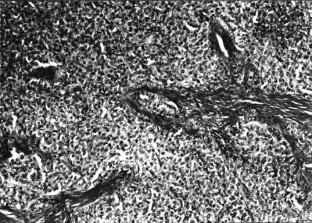

Mobley, D. Diagnosis: Granulosa Cell Tumor. Lab Anim 32, 22–23 (2003). https://doi.org/10.1038/laban0403-22